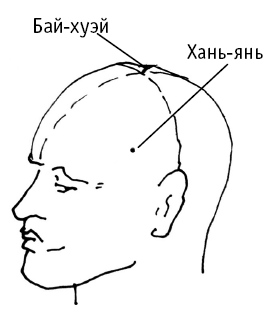

Бай-хуэй («соединение пересечений») расположена в центре темени, на пересечении срединной линии головы с линией, соединяющей кончики ушей.

Воздействие на точку предотвращает головокружение, шум в ушах, помогает при частой одышке, сердцебиении, климактерических неврозах, артериальной гипертонии. Очень важная точка. Она используется так же при поносах, рвоте, недержании мочи, выпадении прямой кишки и матки, опущении внутренних органов; при солнечных ударах, потере сознания; при нервных расстройствах и др.

В случае шума в ушах при повышении давления – работаем с точками на голове: Бай-хуэй, Хань-янь, Лу-си (за ухом), Тянь-чуан.

Бай-хуэй («соединение пересечений») расположена в центре темени, на пересечении срединной линии головы с линией, соединяющей кончики ушей.

Воздействие на точку предотвращает головокружение, шум в ушах, помогает при частой одышке, сердцебиении, климактерических неврозах, артериальной гипертонии. Очень важная точка. Она используется так же при поносах, рвоте, недержании мочи, выпадении прямой кишки и матки, опущении внутренних органов; при солнечных ударах, потере сознания; при нервных расстройствах и др.

В случае шума в ушах при повышении давления – работаем с точками на голове: Бай-хуэй, Хань-янь, Лу-си (за ухом), Тянь-чуан.